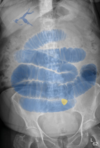

What is being highlighted here?

**Cause of obstruction** ## Footnote There are branching dark lines (gas) projected over the centre of the liver, larger and more prominent towards the hilum, in keeping with pneumobilia. There are centrally located loops of bowel measuring \>3 cm in diameter with valvulae conniventes seen throughout, in keeping with dilated small bowel. There is a calcified opacity projected over the left sacrum in keeping with a large calcified gallstone. The right radiograph shows the pneumobilia marked in dark blue, dilated small bowel marked in blue and gallstone marked in yellow.